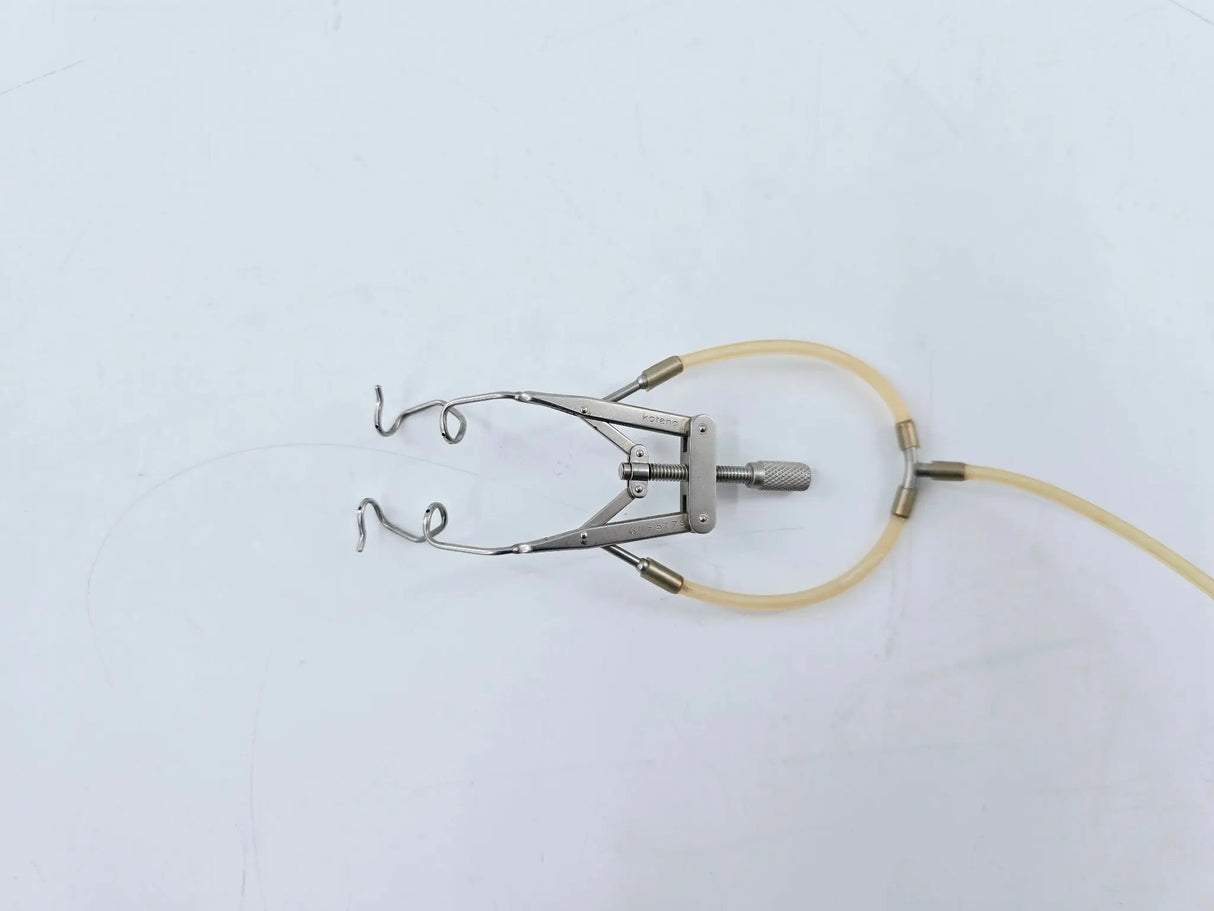

Aspirating Speculum V-Wire, Kratz-Style 3-1/4"

Katena K1-5175 Lieberman Aspirating Speculum V-Wire, Kratz-Style 3-1/4"

For removal of excess fluid from the ocular surface. Supplied with silicone tubing and luer-lock adaptor.

• Model: K1-5175

• Self-Retaining

• Features silicone tubing and luer-lock adapter

• Overall Length (with tubing): 15-1/4 inches